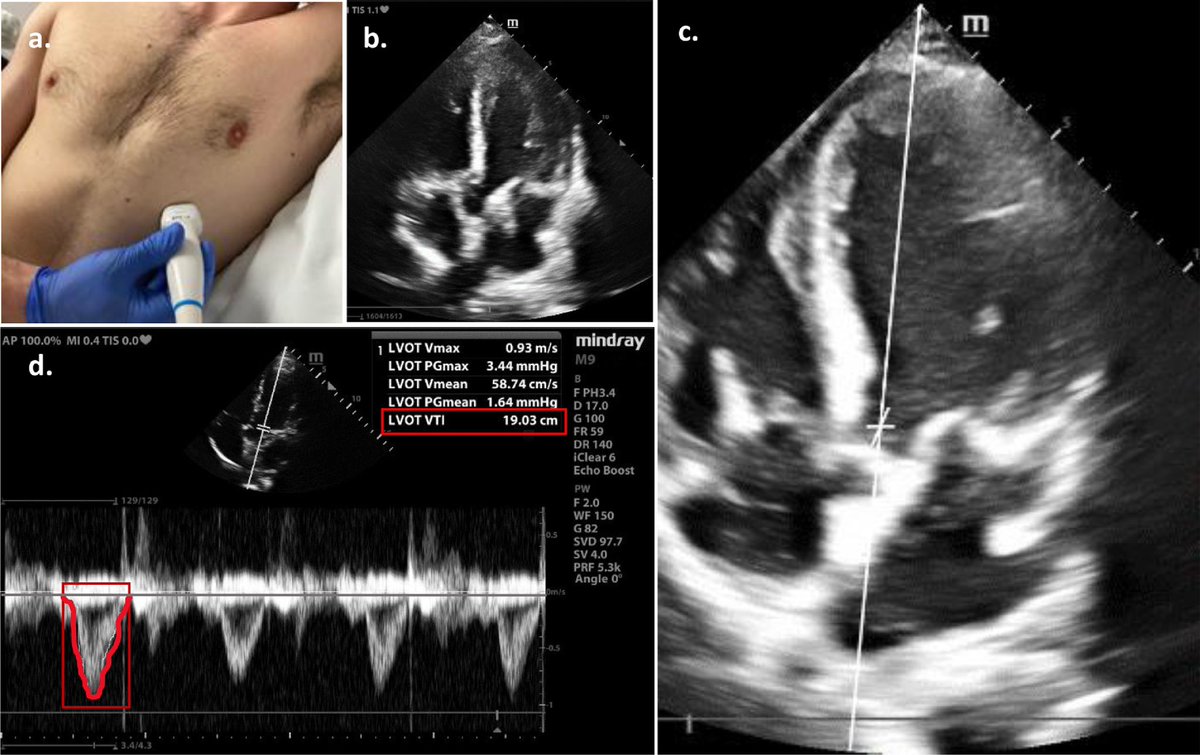

Cardiology fellow at East Carolina University #echofirst #cardiofellow #ACCFIT